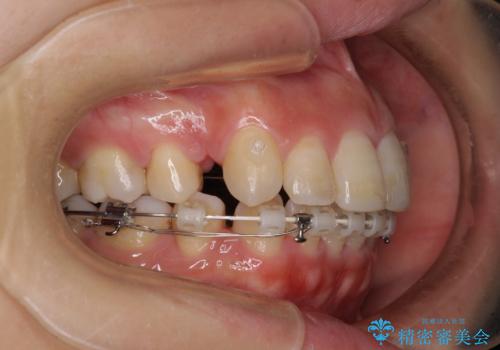

突出した口元が気になる ハーフリンガル装置による抜歯矯正

- ハーフリンガル

- 口元の突出感を気にして来院された患者様です。

通常では上下左右の第一小臼歯4本を抜歯しますが、下顎が左側にシフトしていたため、下顎左側のみ第二小臼歯を抜歯し、正中を合わせながら口元を下げる治療計画としました。

ハーフリンガルは、通常では表側のワイヤー矯正よりも治療期間がかかります。特に今回のように下顎左側をイレギュラーの第二小臼歯抜歯としたため、さらに時間がかかることが予想されました。

実際に治療をおこなってみると、2年を切る短期間で治療を終えることができました。